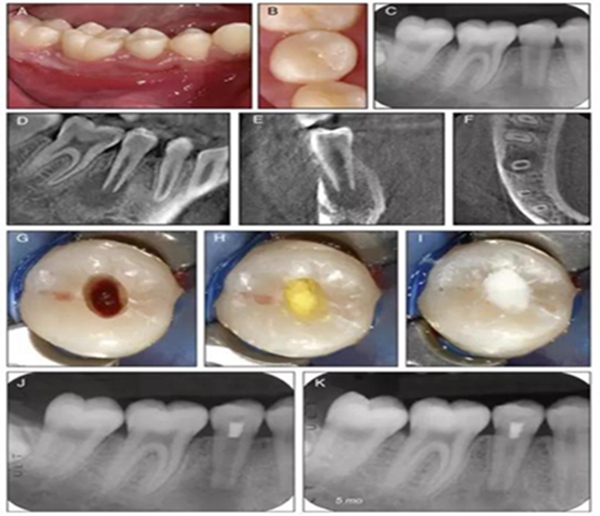

原則上年輕恒牙的牙髓治療應(yīng)盡可能以保存活髓的方式以便不影響牙根繼續(xù)發(fā)育。本文3個(gè)病例均描述了根尖尚未發(fā)育完成的下頜前磨牙被確診為牙髓壞死伴有大面積根尖病損,治療過(guò)程中在根管內(nèi)發(fā)現(xiàn)了部分活髓,而采用活髓切斷后都取得了很好的療效。